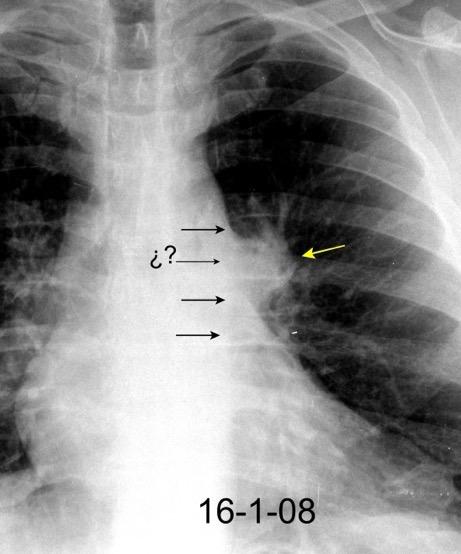

152. SIGNO DEL 1-2-3

Triada de Garland

Ganglios paratraqueales derechos e hiliares bilaterales

95% de pacientes tienen ganglios hiliares bilaterales aislados o con afectación mediastínica (espec. paratraqueal derecho).

Criado E et al. Pulmonary sarcoidosis: typical and atypical manifestations at high-resolution CT with pathologic correlation. Radiographics. 2010